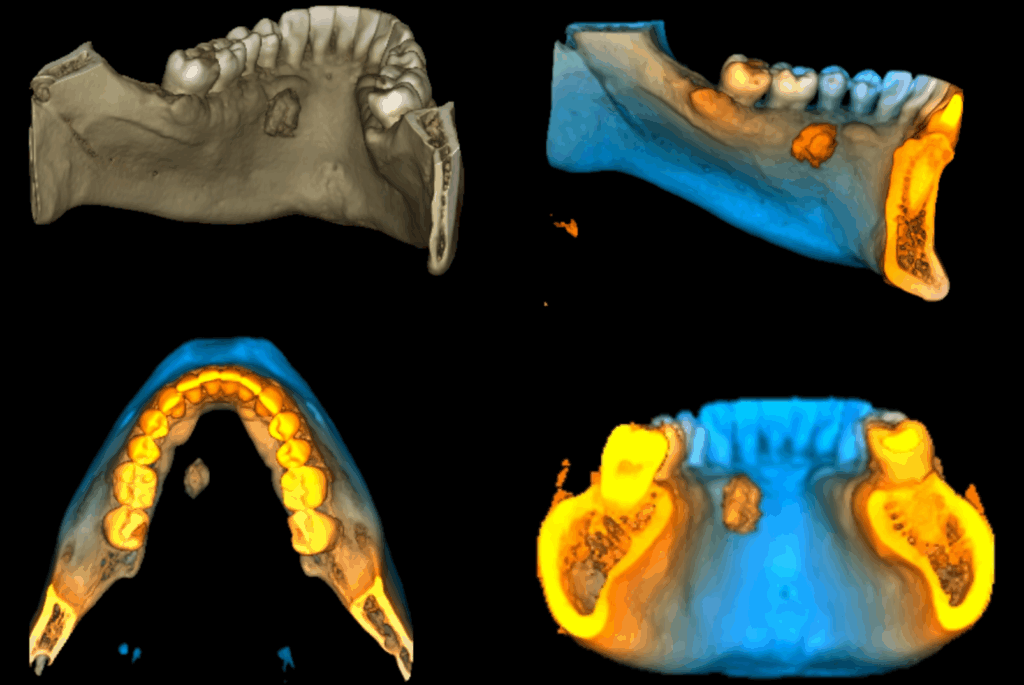

Paciente femenina de 51 años acude al Instituto para realizarse una tomografía volumétrica para rehabilitación oral, a la evaluación de la radiografía panorámica se observa neumatización de ambos seno maxilares, imagen radiopaca proyectada a nivel apical de la pieza 35 compatible con osteoesclerosis idiopática, múltiples restauraciones coronarias, presencia de dos implantes en zona de las piezas 16 y 21.

Radiografia Panorámica

A la evaluación de la tomografía de campo mediano (10 x 10) se observa una imagen hiperdensa que no se evidencia en la radiografía, de forma irregular y limites definidos localizada en tejido blando a nivel de piso de boca y de las piezas 36 y 35 compatible con sialolito submandibular.